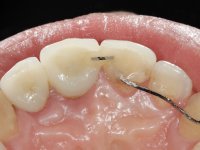

Paciente do sexo masculino, com 29 anos não fumador. Após atendimento hospitalar, na sequência de um traumatismo facial, surgiu na consulta com os dentes 2.1 e 2.2 com extensas fraturas coronais e com exposição pulpar. As fraturas eram justa-ósseas a nível palatino e as raízes apresentavam mobilidade acentuada. Os dentes 1.3,1.2 e 1.1 apresentavam-se ferulizados com um arame ortodôntico. A ferulização abrangia as superfícies vestibulares e palatinas. Os três dentes em conjunto também apresentavam mobilidade. O lábio inferior apresentava-se ainda suturado e a higiene oral era sofrível.

Foi feito o tratamento endodôntico dos dentes 2.1 e 2.2.de imediato, a sintomatologia que o paciente manifestava a isso impunha. Na mesma consulta foi realizada uma extensa gengivetomia com o bisturi elétrico, no sentido de expor os limites cervicais da fratura. Foram colocadas resinas compostas nos remanescentes radiculares com a intenção de reformular a emergência dos tecidos moles. Realizei a impressão dos remanescentes radiculares para confeção em laboratório de uma ponte provisória. A ponte provisória de 2 elementos, apresentava um formato que visava no futuro acomodar o coto dos espigões falsos cotos que iria ser cimentados nos remanescentes radiculares. Apresentava um reforço metálico palatino e dois apoios para os dentes adjacentes, um mesial e outro distal. Os remanescentes radiculares foram preparados para a confeção de dois espigões falso coto fundidos. As linhas de acabamento cervical foram definidas e os canais radiculares desobturados e preparados. A impressão foi realizada com a utilização de tutores de plástico com a técnica de dupla mistura. O afastamento gengival foi feito utilizando pasta de caolino. A ponte provisória foi rebasada em boca com acrílico auto polimerizavel, cimentada provisoriamente sobre as raízes e os apoios colados aos dentes adjacentes. No laboratório foram confecionados os E.F.C. fundidos, tendo o cuidado de preservar espaço para a definição no re preparo dentário da linha de acabamento cervical. Removida a ponte provisória foi feita a cimentação dos E.F.C. fundidos com cimento de ionómero de vidro reforçado com resina. A ponte provisória teve que ser retocada para permitir a acomodação dos cotos e simultaneamente foi readaptada à redefinida linha de acabamento cervical. Durante 2 meses a ponte provisória acompanhou a estabilização periodontal das raízes traumatizadas e simultaneamente conseguiu a maturação da arquitetura gengival.